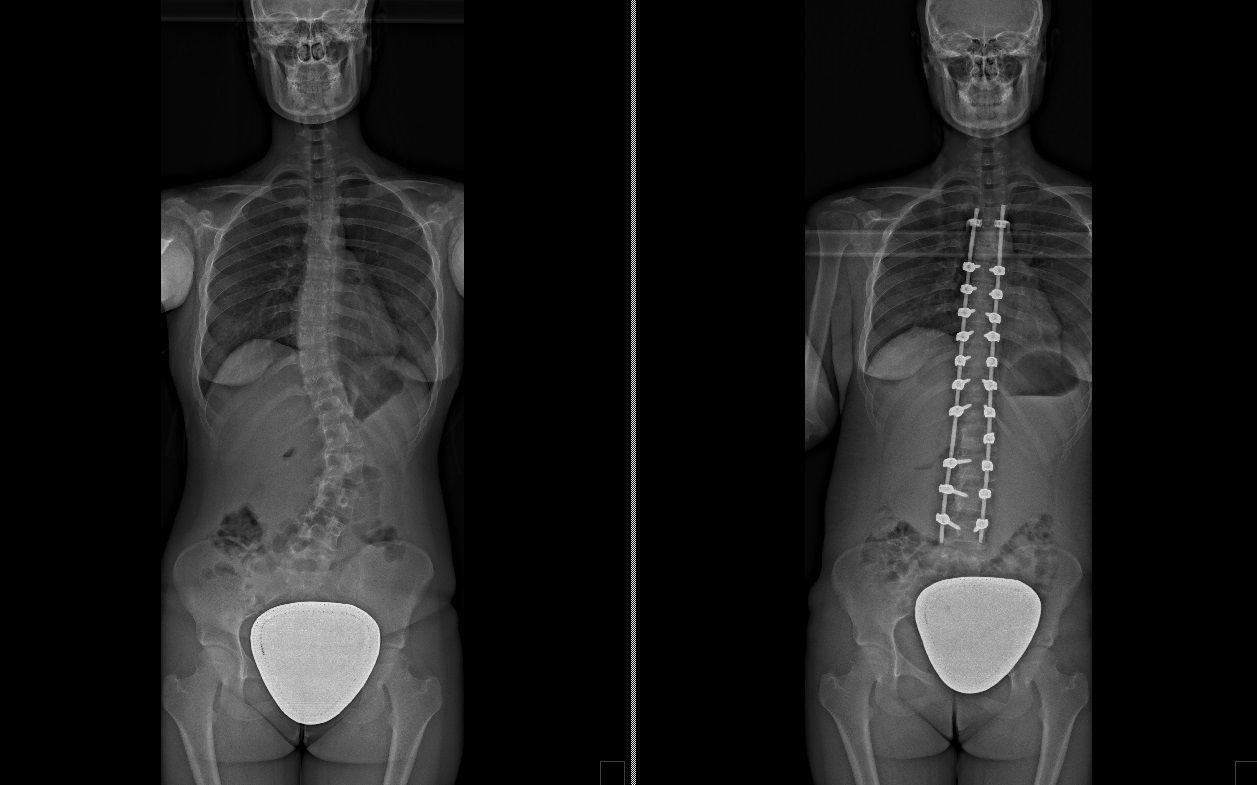

Laureato in Medicina e Chirurgia presso l'Università degli Studi di Napoli Federico II nel 2011, Specializzato in Ortopedia e Traumatologia presso la stessa Università nel 2017. Da subito ho dedicato i miei studi all'ambito della chirurgia vertebrale e della neurochirurgia. Infatti ho frequentato per 9 mesi tra il 2015 ed il 2016 i reparti di Neurochirurgia dell'IRCCS Neuromed di Pozzilli (IS) per apprendere le tecniche di trattamento delle Patologie della Colonna Vertebrale. Da allora il mio principale interesse è rivolto al trattamento conservativo e, dove necessario, chirurgico delle deformità della colonna vertebrale, sia dell’età dell’accrescimento che degenerative dell’adulto: scoliosi, dorso curvo, spondilolisi, spondilolistesi. Ulteriori campi di interesse sono il trattamento di lombalgia e lombosciatalgia, ernia del disco, stenosi del canale vertebrale, fratture vertebrali traumatiche o da osteoporosi (vertebroplastica), terapia del dolore osteoarticolare mediante tecniche mininvasive (radiofrequenze). Dal 2017 sono Consulente presso IRCCS Neuromed di Pozzilli (IS) con incarico di Responsabile del Centro per la Diagnosi e Cura delle Deformità Vertebrali e Scoliosi, dove svolgo la mia attività chirurgica in regime di convenzione. Svolgo la mia attività chirurgica in regime di solvenza e di convenzione assicurati presso la Clinica Ruesch di Napoli. Continuo costantemente la mia formazione con esperienze di perfezionamento nazionali ed internazionali. Infine, dal 2020 sono Docente per l'Università degli Studi di Roma "La Sapienza".

• Chirurgia vertebrale

Foto e video